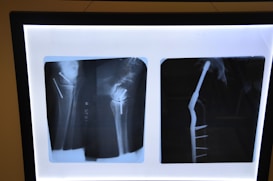

At clínica maxilofacialcom, we specialize in advanced TMJ and maxillofacial surgery, combining expert care with cutting-edge technology to relieve your jaw pain.